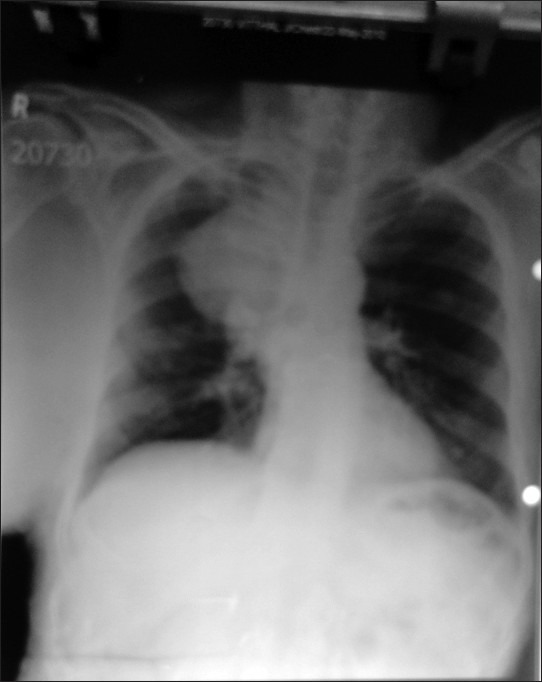

Malignant peripheral nerve sheath tumor (MPNST) is a malignant spindle cell tumor of the soft tissue thought to be derived from the components of nerve sheath. MPNSTs are mainly located in the buttocks, thighs, brachial plexus, and paraspinal region. The objective of this article is to describe a case of neurofibromatosis type 1 who developed neurofibrosarcoma of the right lateral thoracic nerve with thoracic meningoceles, a rare coincidental finding which has not yet been reported in the English medical literature, and how both the conditions were managed in the same sitting.